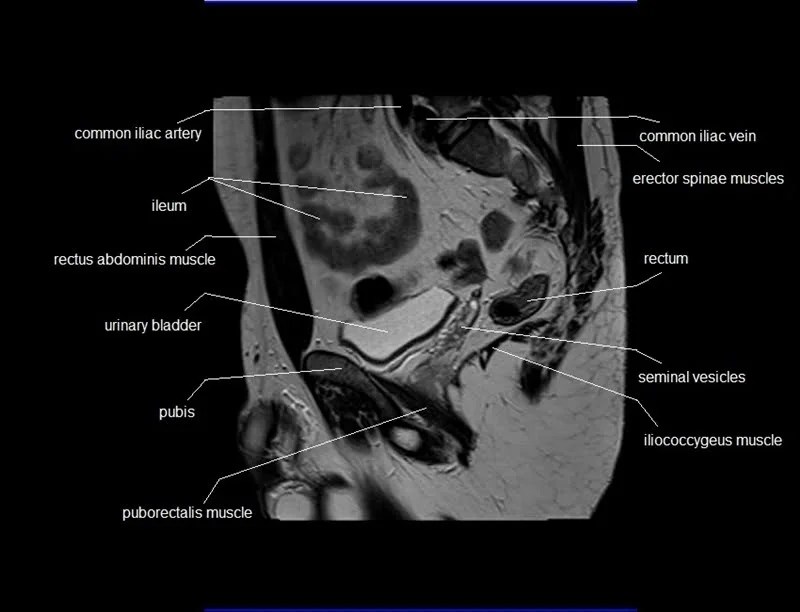

Mri Anatomy Male Pelvis . Anatomy of the male pelvis (prostate, bladder, genital organs, perineum) on mr imaging, male pelvis, mri, urinary system. Mri techniques for imaging the male pelvis; Knowledge of normal pelvic anatomy on mri is critical for proper interpretation, in particular the standard visceral organ appearances, commonly encountered variants, and. The gonadal vessels refer to the testicular artery and testicular vein in males and the ovarian artery and ovarian vein in females. This article reviews normal male pelvic floor anatomy and how it differs from the female pelvis; Radiologists have historically imaged the male pelvis using many methods. This webpage presents the anatomical structures found on male pelvis mri. Penis, testis, prostate, urinary bladder. This mri male pelvis axial cross sectional anatomy tool is absolutely free to use. Use the mouse scroll wheel to move the images up and.

Knowledge of normal pelvic anatomy on mri is critical for proper interpretation, in particular the standard visceral organ appearances, commonly encountered variants, and. Penis, testis, prostate, urinary bladder. Mri techniques for imaging the male pelvis; Use the mouse scroll wheel to move the images up and. This article reviews normal male pelvic floor anatomy and how it differs from the female pelvis; Anatomy of the male pelvis (prostate, bladder, genital organs, perineum) on mr imaging, male pelvis, mri, urinary system. This mri male pelvis axial cross sectional anatomy tool is absolutely free to use. The gonadal vessels refer to the testicular artery and testicular vein in males and the ovarian artery and ovarian vein in females. Radiologists have historically imaged the male pelvis using many methods. This webpage presents the anatomical structures found on male pelvis mri.

Mri Anatomy Male Pelvis This article reviews normal male pelvic floor anatomy and how it differs from the female pelvis; This webpage presents the anatomical structures found on male pelvis mri. Use the mouse scroll wheel to move the images up and. Anatomy of the male pelvis (prostate, bladder, genital organs, perineum) on mr imaging, male pelvis, mri, urinary system. This article reviews normal male pelvic floor anatomy and how it differs from the female pelvis; The gonadal vessels refer to the testicular artery and testicular vein in males and the ovarian artery and ovarian vein in females. Radiologists have historically imaged the male pelvis using many methods. This mri male pelvis axial cross sectional anatomy tool is absolutely free to use. Mri techniques for imaging the male pelvis; Penis, testis, prostate, urinary bladder. Knowledge of normal pelvic anatomy on mri is critical for proper interpretation, in particular the standard visceral organ appearances, commonly encountered variants, and.